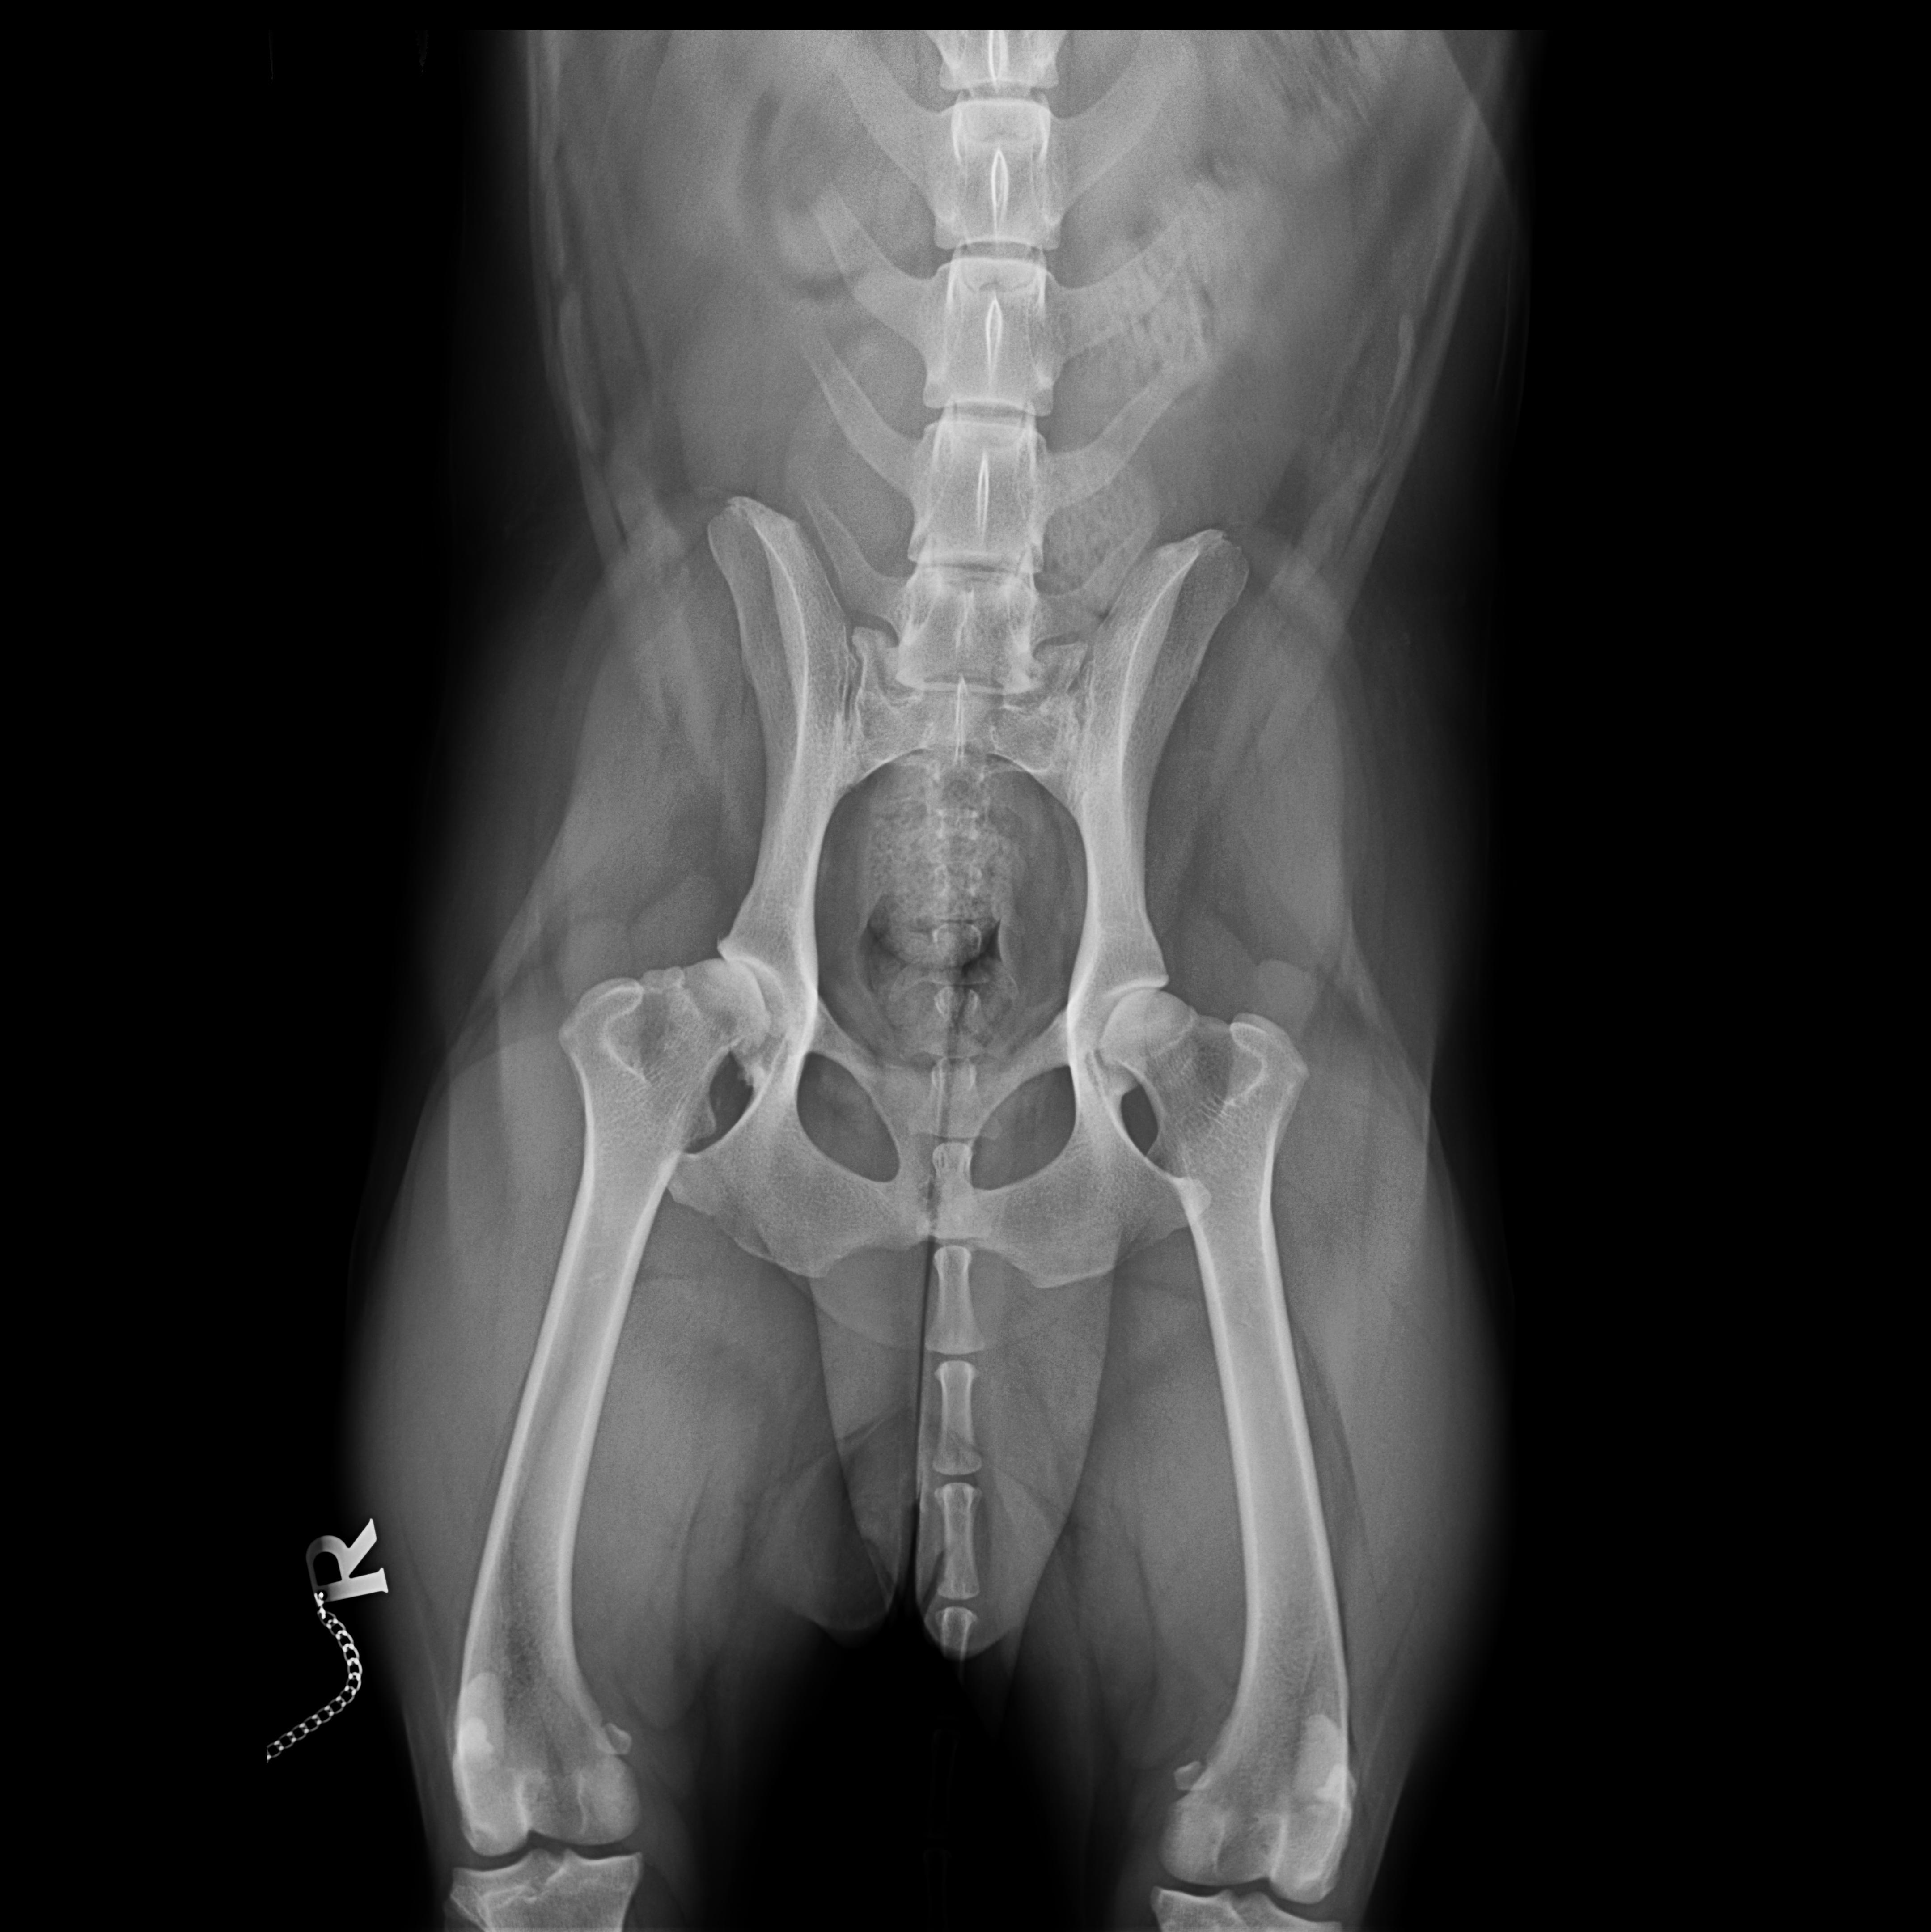

Bei genauerer Untersuchung des gesamten Bewegungsapparates im Gehen, Traben und auch durch Abtasten wurde allerdings schnell klar, dass der rechte Ellbogen nicht Bonnies einziges Problem war. Bonnie ging beim Vorlaufen (Gangbildanalyse) insgesamt recht steif, vorne übermäßig breit, hinten sehr eng und mit der Hinterhand nach rechts versetzt. Die Lahmheit zeigte sich im Trab deutlicher als im Schritt, beim Abtasten reagierte Bonnie druckschmerzhaft am rechten Ellbogen, an einzelnen Zehengelenken vorn beidseits, an den Schultergelenken, der gesamten Wirbelsäule, der rechten Hüfte und geringgradig an beiden Kniegelenken. Alle auffälligen Stellen wurden daraufhin geröntgt. Röntgenologisch fanden wir bei Bonnie, entsprechend der Schwere der Befunde absteigend geordnet:

- Zehengelenksarthrosen vorn beidseits

- Hüftgelenksdysplasie und -arthrosen beidseits